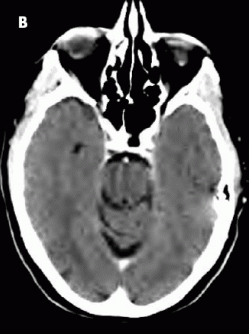

In this patient, treatment with R-CHOP chemotherapy for 6 cycles resulted in excellent clinical and radiological response (B).